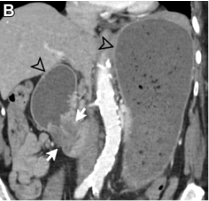

In the pure form, the appearance can range from ill-defined fat stranding and inflammatory change in the groove between the pancreatic head and duodenum, to frank soft tissue in the groove.

This soft tissue often has a “sheetlike” curvilinear crescentic shape that is best appreciated on coronal images.

If multiphase imaging is performed, this soft tissue tends to show increasing delayed enhancement as a result of a significant fibrotic component.

There can be of the medial duodenal wall (particularly on the coronal images), and small cysts are a common feature either within the thickened duodenal wall or the pancreaticoduodenal groove itself.